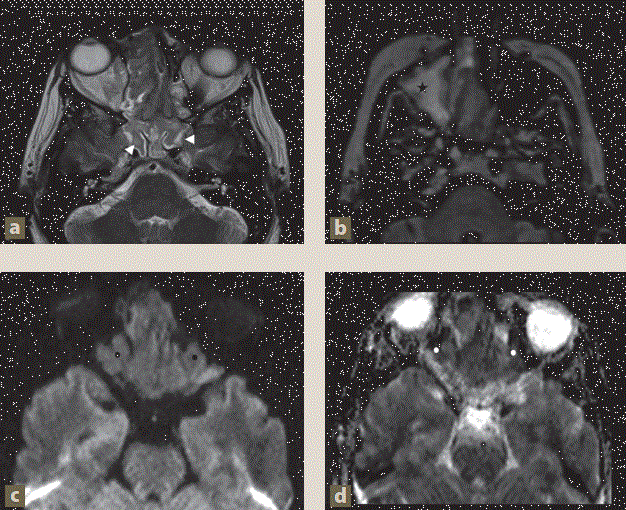

Imagen: Prado Hernández et al.

Figura 4 a) Tumor nasal con extensión intracraneal en reconstrucción 3D. b) y c) Angiografía diagnóstica (AX DX) y embolización (técnica olla a presión), posición lateral con road mapping: cateterización de la arteria maxilar interna con extremo distal en la arteria angular, donde se observa “Blush tumoral” y una prominente vascularización en fases arterial temprana y tardía. d), e) y f) Embolización con ascenso de coils (tapón) (puntas de flecha), embolización con Onyx 18 (asteriscos) y mezcla de histoacryl-lipiodol (flechas delgadas). g) Material embolizante con exclusión de la vascularización tumoral. h) Imagen previa a la embolización. i) Imagen posterior a la embolización (control).